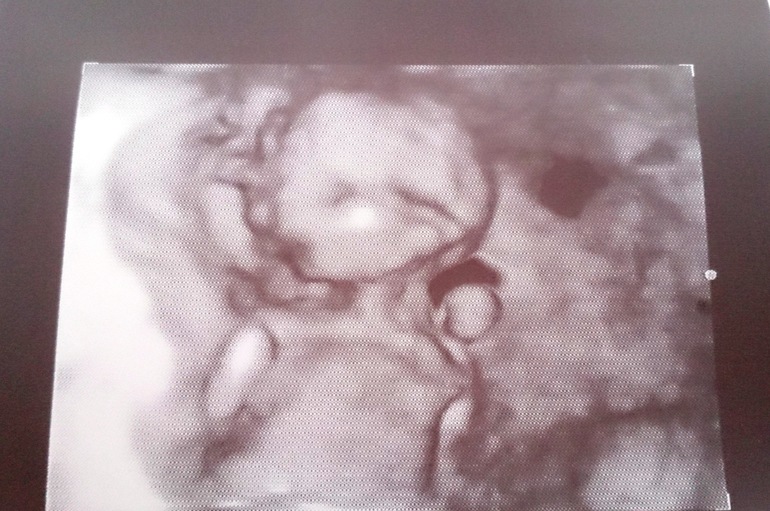

Вот фото узи 14 недель и 5 дней:

Через 2 недели случайно записалась я на 3д узи. Уже с конкретной целью - рассмотреть пол. Дали мне фотки (почему-то чёрно-белые), показали всё на экране, однако суровый дядечка-узист сказал, что "он сам кое-что видел, но мне не скажет, потому что неточно ещё". Потрясающе)))

Результаты УЗИ в 16 недель и 5 дней:

БПР - 34,9мм, вес - 157г, ЧСС - 145, по органам и структурам без патологий; плацента по задней стенке на 34,7 выше внутреннего зева, вод - норма, шейка - в порядке.

В общем - выдохнули!!!